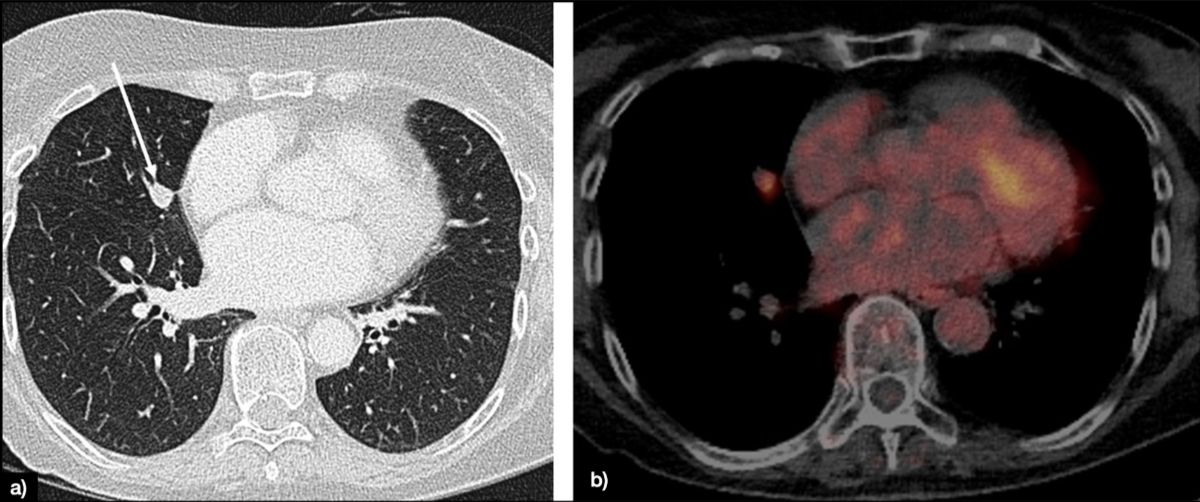

The clinical staging of lung cancer (currently in its 8th edition [120]) rests on either CT or CT in conjunction with PET. The local tumour extent is mainly determined by multiplanar CT measurements. In cases with bronchial obstruction, PET-CT can help to distinguish the lesion boundaries from atelectasis. Lymph node assessment in CT is mainly based on size criteria. Although lymph nodes vary in size depending on their location, a general threshold is deemed to be 1 cm in short-axis diameter. Additional criteria comprise texture (i.e. enhancement patterns) and shape. PET-CT is more sensitive for the nodal assessment and the depiction of distant metastasis. If metastatic spread to the brain is suspected, additional MR imaging is required to determine the M stage (figure 1).

Figure 1Lung solid nodule of 12 mm in the middle lobe (white arrow), classified as Lung-RADS 4A (suspicious) (A). The patient underwent PET-CT, showing fluorodeoxyglucose (FDG) avidity only of the nodule (B).

Lymph node assessment in CT is mainly based on size criteria. Although short axis thresholds vary depending on the location, a general threshold is deemed to be 1 cm in short-axis diameter. Additional criteria comprise texture (i.e. enhancement patterns) and shape [15, 16]. By comparison, PET-CT is more sensitive for the nodal assessment and the depiction of distant metastasis. In suspected tumour spread to the brain, additional MR imaging is required. An overview of the pros and cons of the various modalities is given in table 1. There are no established protocols for follow-up surveillance imaging after curative therapy, but it is advisable to consider annual imaging for at least the initial 5 years.